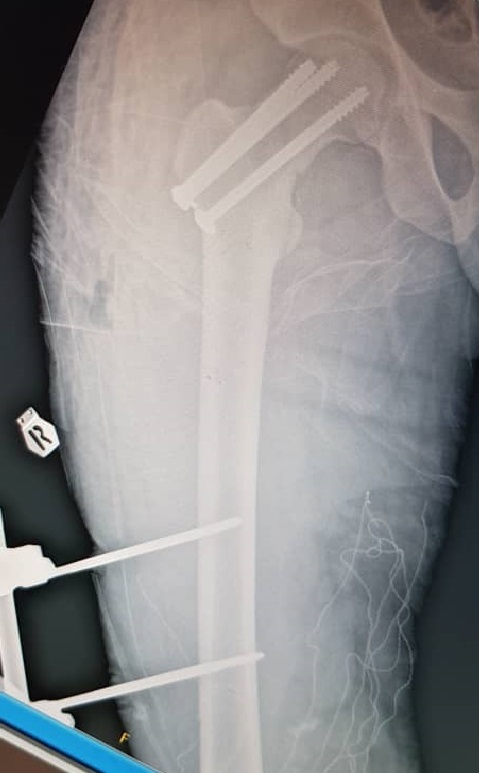

Initial management involved screw fixation of the femoral neck, wound debridement of the right thigh, and placement of an external fixator across the right knee (Figures 4 and 5), followed by a one-week course of intravenous cefuroxime. By January 2021, the right leg had become gangrenous and deemed nonviable. Right above-knee amputation (AKA) with adductor myodesis was performed, followed by intravenous cefuroxime for another week.